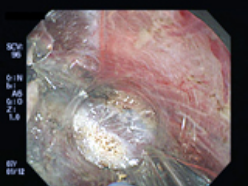

早期大腸癌に対するESD

2.当科が開発した先端細径透明フード(STフード)とヒアルロン酸ナトリウム局注液を使用して、内視鏡下に電気メスで病変を剥離していきます。